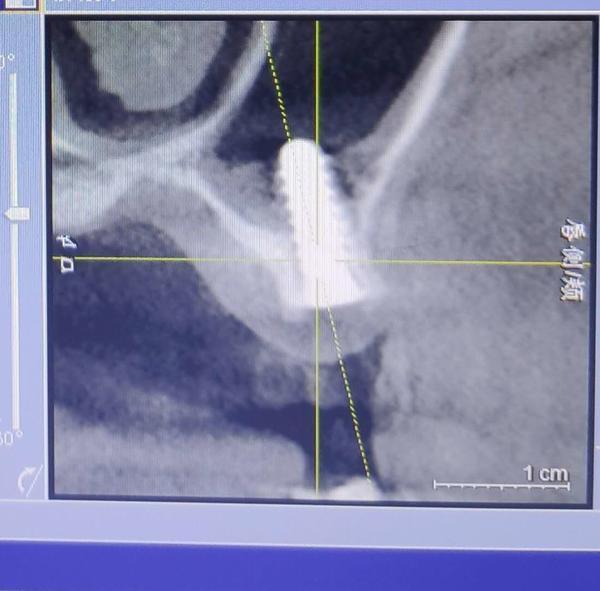

2019年下半年,在出現(xiàn)了不適反應(yīng)后,葉女士到沈陽(yáng)一家部隊(duì)醫(yī)院口腔門(mén)診求醫(yī)。經(jīng)CT等檢查,她才發(fā)現(xiàn),原來(lái)有一顆種植體已經(jīng)進(jìn)入了她的上頜竇腔。

葉女士做出的影像檢查結(jié)果顯示,其中一顆植體已經(jīng)進(jìn)入上頜竇腔內(nèi)。

“有大醫(yī)院醫(yī)生告訴我,這就是說(shuō),種植體把我上頜竇腔打穿,口腔和鼻腔連通了!”葉一帆說(shuō),她隨后了解得知,袁克偉并不具備種植牙的技術(shù)水準(zhǔn),而且執(zhí)業(yè)地點(diǎn)也不在天麗口腔,且天麗口腔診所也不具備種植牙這一診療項(xiàng)目,“我是被他當(dāng)成小白鼠了”。

2019年7月,在出具的診斷證明上,沈陽(yáng)市當(dāng)?shù)匾患胰揍t(yī)院的知名口腔診療專(zhuān)家說(shuō),該種植體已經(jīng)進(jìn)入上頜竇腔,需要取出。